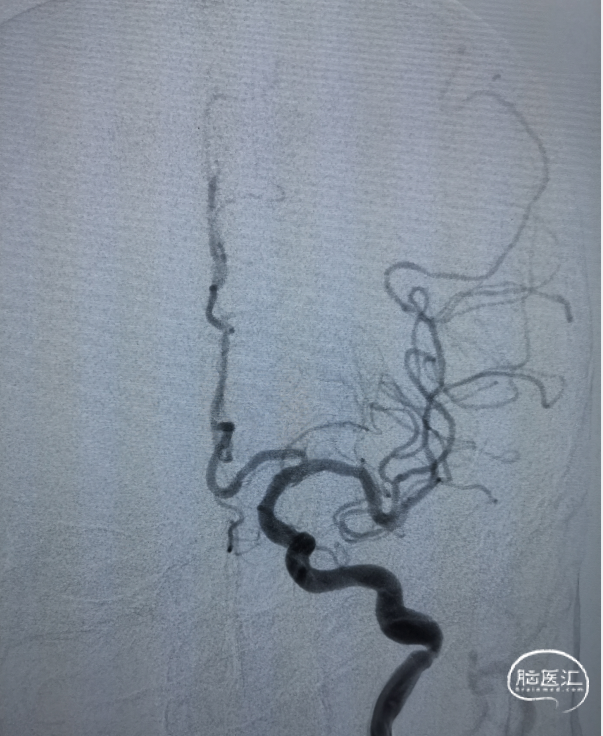

右侧颈动脉造影未见向左侧代偿。

左侧颈动脉造影提示左侧颈内动脉末端闭塞。

微导管置入左侧大脑中动脉M2段造影确认真腔。

置入一枚5*30mm 取栓支架造影。

充盈BGC球囊抽拉结合取栓一次。